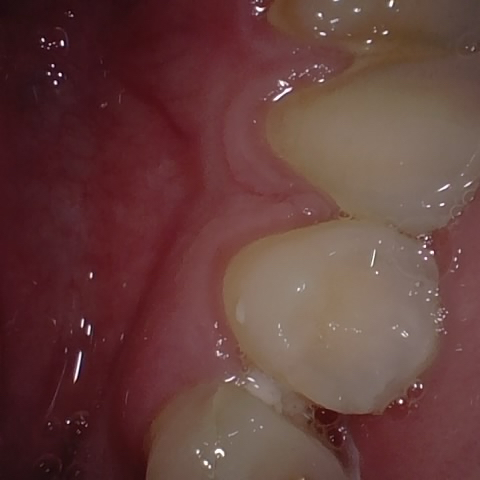

Annotated as "Good"